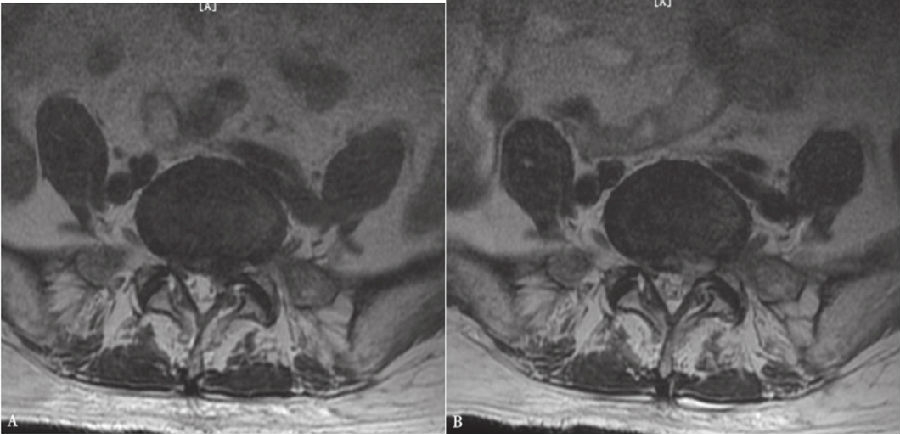

9. 术后复查MRI。(图43、图44)

图43 术前和术后MRI轴位对比

A. 术前腰椎MRI轴位;B.术后腰椎MRI轴位

图44 术前和术后MRI核磁共振矢状位对比

A. 术前腰椎MRI矢状位;B.术后腰椎MRI矢状位